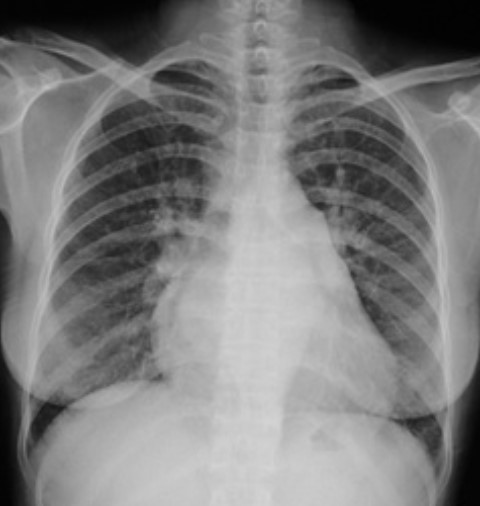

3.根據(jù)下圖請做出正確診斷

A.正常心臟

B.心肌?。ㄆ沾笮模?/p>

C.風(fēng)濕性心臟病(梨型心)

D.主動脈型心(靴型心)

答案提示:【該題針對“ X線-心臟增大(二尖瓣型、主動脈型和普大型) ”知識點(diǎn)進(jìn)行考核】